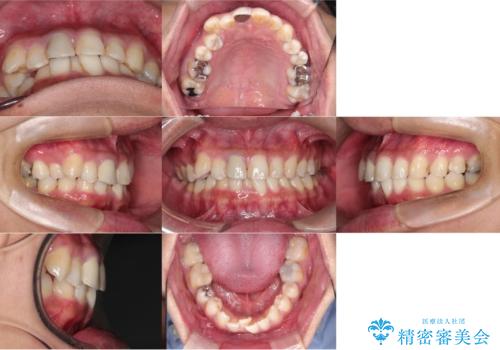

- 30代男性

- 1年9ヶ月

- 10-30回

- 「八重歯と歯のでこぼこを治したい」を主訴に来院された患者様です。

歯は抜かずに奥歯の遠心移動とIPRで八重歯とでこぼこを改善しました。

インビザラインはご飯と歯ブラシ以外はマウスピースをつける矯正です。

使用時間をきちっと守っていただければ、歯のでこぼこなど綺麗に治すことが出来ます。